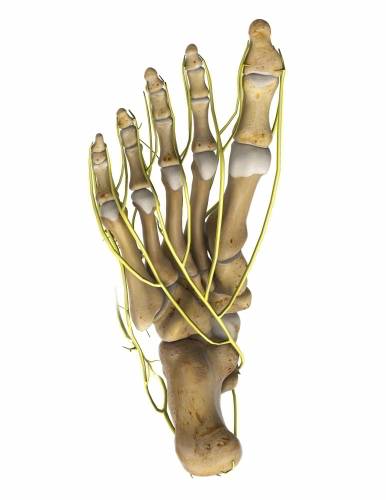

Das Morton Neurom ist eine recht häufige Folge einer Spreizfußfehlstellung. Am häufigsten ist ein Morton Neurom zwischen dem 3. und 4. Zeh zu finden, etwas seltener zwischen dem 2. und 3. Zeh. Dabei stellt die Großzehe den 1. Zehenstrahl dar und der kleine Zeh den 5. Zeh.

Das Morton Neurom entsteht meist vor dem Hintergrund eines Spreizfußes. Die Fehlstellung der Mittelfußknochen ist die Folge eines durchgetretenen vorderen Fußgewölbes. Die Zehenstrahlen im Mittelfuß – die sogenannten Metatarsalen – sind durch die Spreizfußfehlstellung verlagert und zeigen fächerförmig nach außen. Dadurch üben sie bei der normalen Abrollbewegung beim Gehen einen viel stärkeren Druck auf die an der Fußsohle verlaufenden Nerven aus. Durch diese dauernde Reizung entzündet sich der Nerv. Insbesondere die bindegewebige Hülle des Nerven schwillt an. Das Morton Neurom ist also ein Nervenkompressionssyndrom. Es entsteht durch die Einengung des Mittelfußnerven (Entrapment), der zwischen den Zehenstrahlen verläuft. Zusätzlich kann eine schmerzhafte Schleimbeutelentzündung (Bursitis) in der Umgebung der Nerven zusätzliche Schmerzen verursachen.

Die veränderte Belastung des Vorfußes durch den Verlust des Quergewölbes führt zu einer mechanischen Reizung des Hautnervs an der Fußsohle. Durch die langanhaltende Reizung verdickt sich die bindegewebige Hülle und drückt auf den Nerv. Der Patient leidet unter Schmerzen und Taubheitsgefühlen im Fuß.